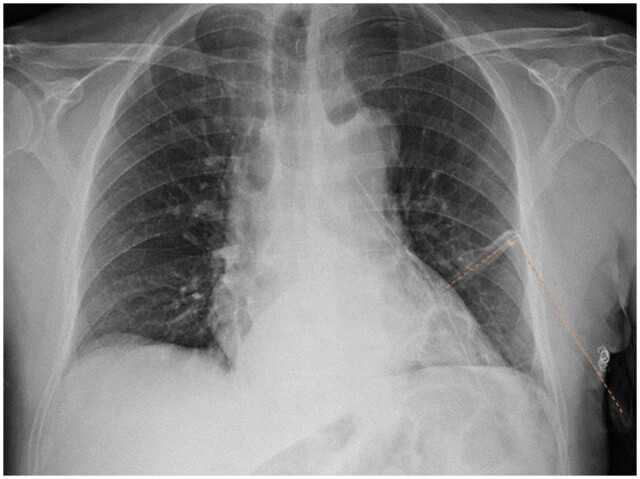

Figure 2:

Examples of use of T-tube after uniportal video-assisted thoracic surgery on X-ray. (a) Right wedge resection; (b) right lower lobectomy; (c) left mediastinal biopsy; and (d) bilateral lung metastasectomy (wedge resections).